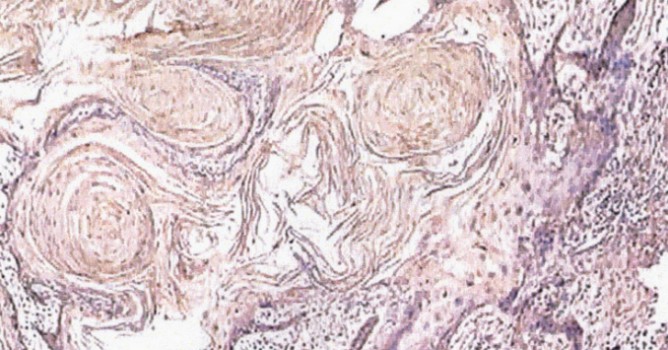

Пока исследования сосредоточены на опухолях поджелудочной железы, самый распространённый вид которых, поджелудочные протоковые аденокарциномы, являются причиной более чем 130 000 смертей в год (Европа и US).

Исследователи использовали NetRank для анализа 20000 белков, чтобы определить примерные показатели их выживаемости. После чего были определены 7 белков, способных помочь в оценке «агрессивности» опухоли. А эта оценка — прямое руководство для врачей, стоит использовать химиотерапию, или нет.